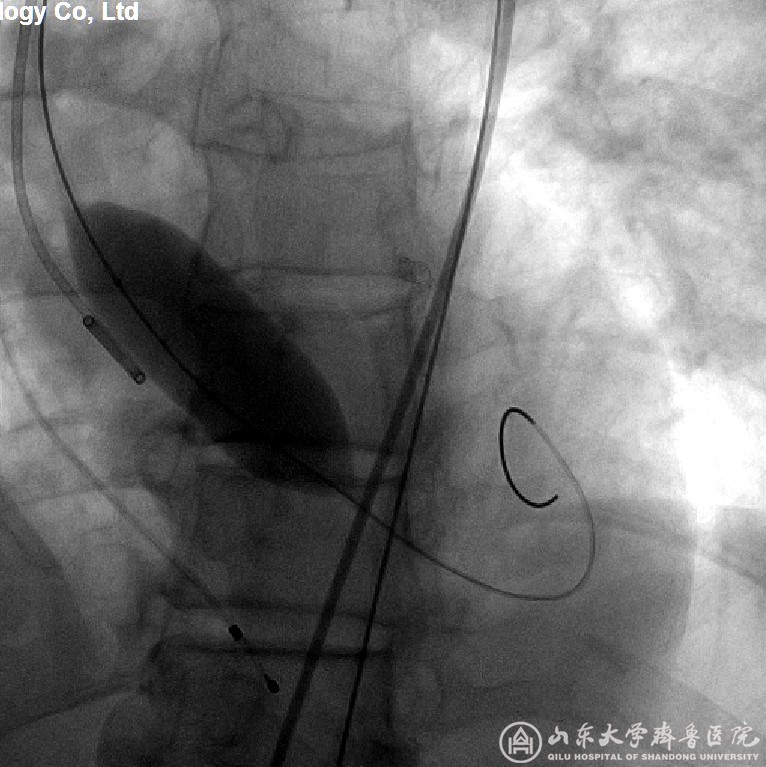

图3 (患者3)球囊扩张狭窄的主动脉瓣